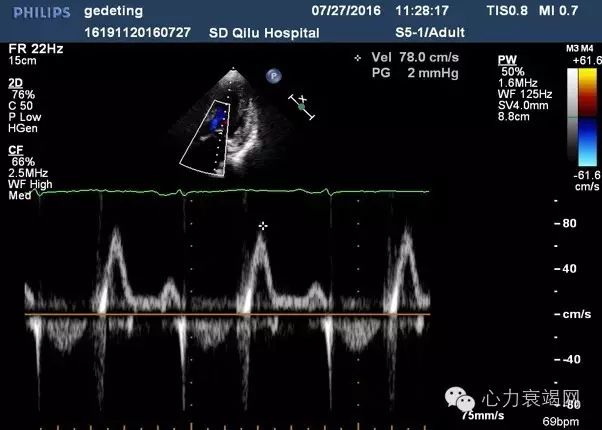

【辅助检查】—心脏超声

肺动脉高压(中度)

E/e’=21舒张功能减低

IVS 15mm,LVPW 14mm,左室侧壁15mm 心尖部13mm;左室心肌回声不均匀;LVEF 35% ,双房扩大,肺动脉高压(中度)E/e’=21 舒张功能减低

▶舒张功能指标减低